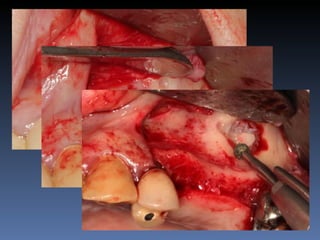

Plano de tratamento: Reabilitação com 1 bloco “onlay”

autógeno proveniente do Ramo de Mandíbula; para

reabilitação futura com implante endo-ósseo.

Descorticalização   Fixação do bloco “onlay”

BOX 1